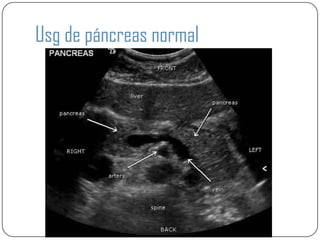

Usg de páncreas normal